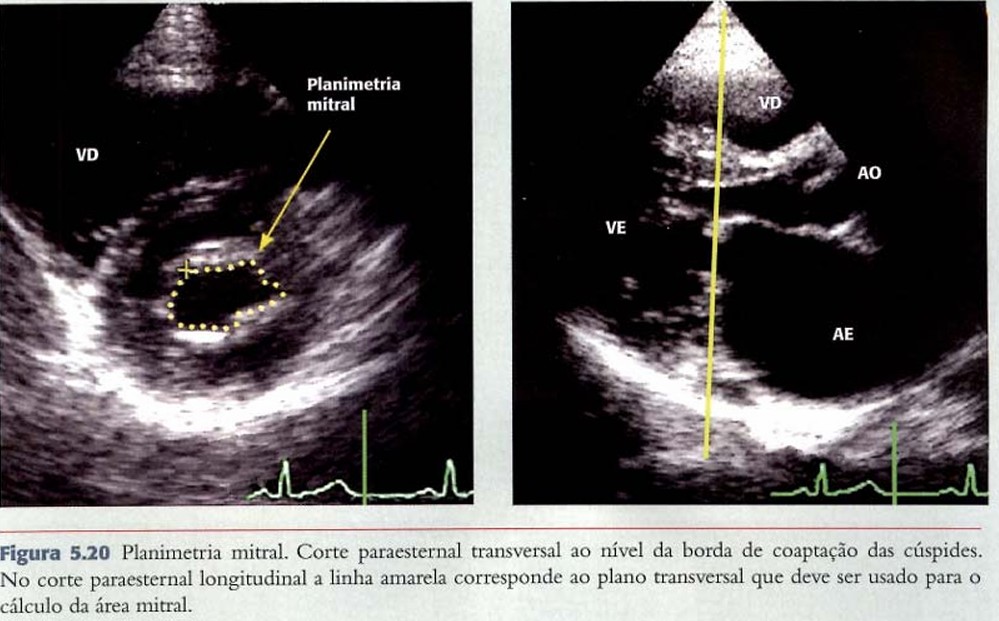

PLANIMETRIA:

Consiste na medida direta do orifício valvar pela ecocardiografia bidimensional e, diferentemente dos outros métodos, não sofre influência das condições de fluxo, complacência ventricular e atrial ou de outras valvopatias associadas.

Em teoria, é a medida mais fiel e considerado o “padrão ouro” para a avaliação da área valvar. Idealmente, o traçado do orifício valvar, incluindo a região comissural, é realizado no eixo curto da janela paraesternal.

Aqui, o grande cuidado técnico é assegurar que a medida está sendo realizada no plano de coaptação dos folhetos.

A planimetria não deve ser realizada em valvas muito deformadas ou com presença de calcificação excessiva em razão da dificuldade em delimitar a borda de coaptação.

Outro detalhe a ser lembrado é que um ganho excessivo pode subestimar a área da valva, particularmente quando os folhetos estão espessados ou calcificados.